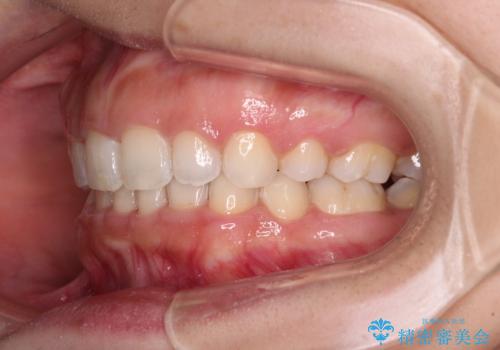

上下顎ともに前突しており、特に上顎は著しい突出感でした。

また、下顎歯列には左右差があり、非対称な抜歯が必要と判断されたため、治療は困難なものとなりました。

それでも根気強く通院してくださり、横からの顔貌の印象が大きく改善され、スムーズに口が閉じられるようになりました。